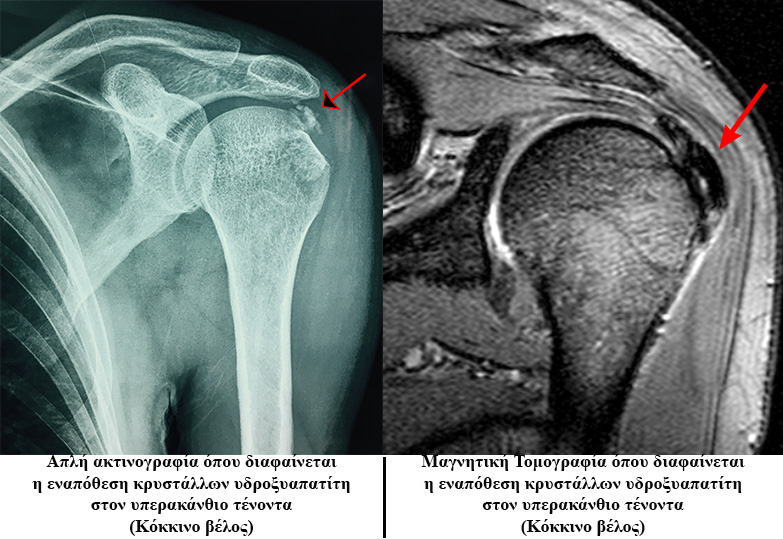

Είναι η εναπόθεση αλάτων-κρυστάλλων ασβεστίου (υδροξυαπατίτη) στο εσωτερικό της μάζας του υπερακανθίου κυρίως τένοντα.